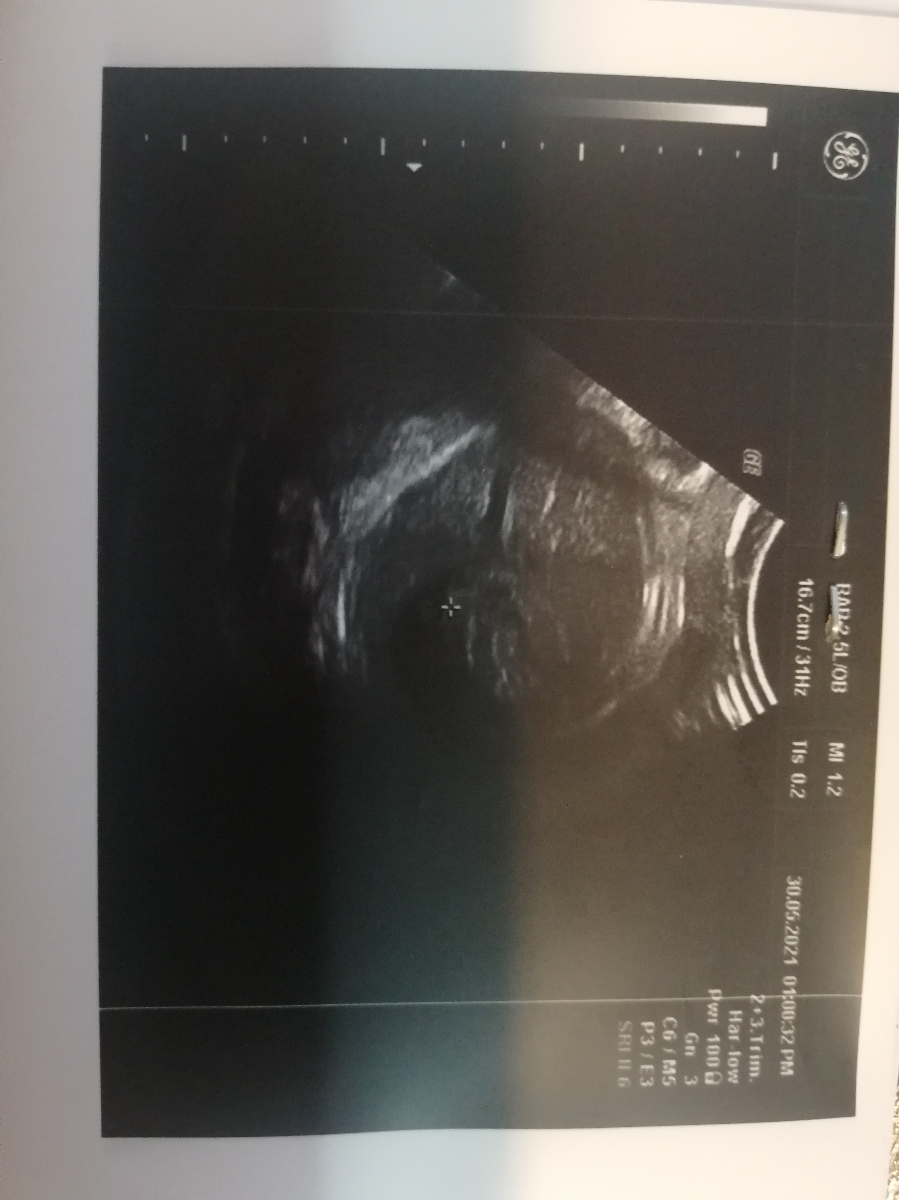

بله الان عکسشو میفرستم خدمتتون

خانم دکتر عزیز سلام من مجدد سونویی که گفتین رو انجام دادم میشه ببینید

دکتر سونوگرافی گفت فقط دور شکمش رشدش کم بوده، جای نگرانی داره به نظرتون

احسنت به شما که پیگیر هستید 💕خوشبختانه اختلال در خونرسانی جفتی دیده نشده و این اختلاف رشدی دیگر نگران کننده نیست. توصیه های تغدیه ای که می گویم را رعایت کنید انشالله این مساله هم جبران می شود. مصرف مایعات و به ویژه آب را افزایش داده و همچنین انواع گوشت ها را به شکل کبابی مصرف کنید. انواع حبوبات، به ویژه لوبیا و عدس را بیشتر مصرف کنید. البته به شرط آنکه از ۲۴ ساعت قبل از مصرف حبوبات را خیس کنید تا نفخ آنها به صورت کامل گرفته شده و باعث اذیت شدن معده شما نشوند. قارچ گزینه مناسبی است که به وزن گرفتن جنین کمک می کند، بنابراین آن را در رژیم غذایی خود بگنجانید. البته از خوردن قارچ خام خودداری کنید. آجیل خام و انواع مغزیجاتی که خام هستند را به صورت روزانه مصرف کنید و اگر برای معده شما سنگین بوده و باعث اذیت شدن سیستم گوارشی میشوند، می توانید آنها را پودر کرده و سپس خرما را بدون پوست در پودر به دست آمده بغلطانید. در روز به این شکل چند عدد خرما همراه با پودر به دست آمده از مغزیجات را مصرف کنید. در صورت صلاحدید پزشک و در صورتی که سطح قند خون شما بالا نباشد، مکمل لیدی نیز را شروع کرده و از آن در طی بارداری خود استفاده کنید. پودری که پزشکتان تجویز کرده احتمالا همان لیدی میل است. به پهلوی چپ بخوابید. اگر در آزمایش قند خون هفته ۲۸ بارداری، همه چیز طبیعی بوده است، می توانید بلافاصله بعد از صرف غذا یک پیاله پر بستنی بخورید. البته در این کار زیاده روی نکنید، زیرا ممکن است شما را مستعد به افزایش قند خون و دیابت بارداری نماید. مصرف به اندازه از کنجد، موز، مغز تخمه خام و همچنین میوه آووکادو، راهکار موثر دیگری است که بهبود وزن گیری جنین کمک می کند. همچنین حتماً برای حداقل چند نوبت در هفته تخم مرغ و ماهی (ماهی دو بار در هفته و از انوع کم جیوه)، بخورید💕